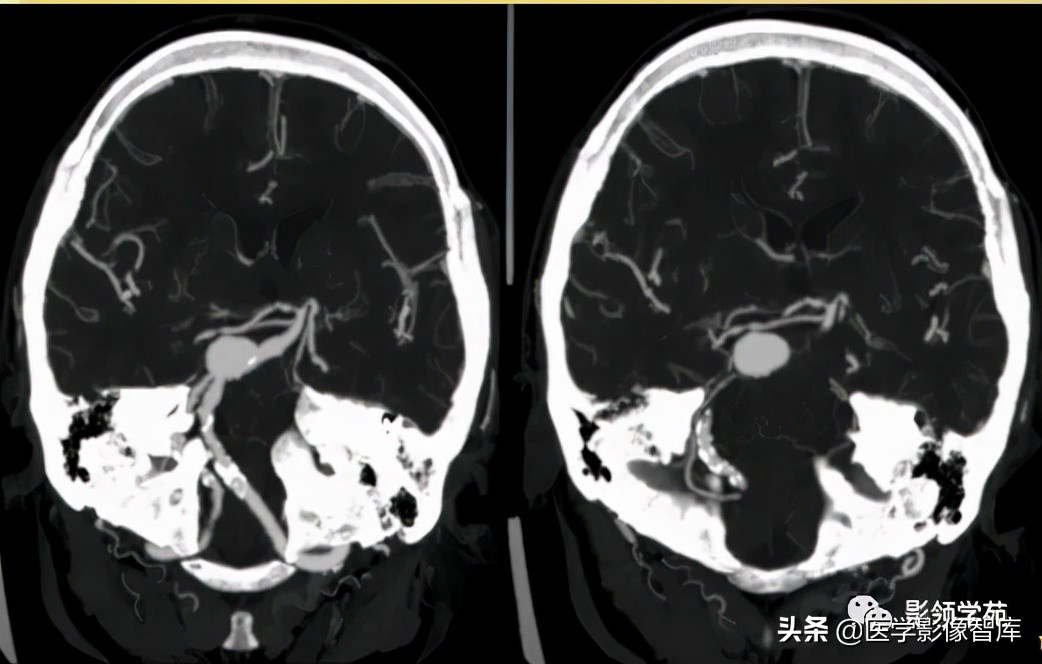

女 72岁,发现糖尿病3年余

鞍上区见一团块状稍高密度影,边界尚清,密度均匀。

鞍上右上方见一类椭圆形流空影。

病灶明显强化(瘤内血栓未强化),边界清楚,与右侧颈内动脉海绵段分界不清。垂体大小、形态未见异常。